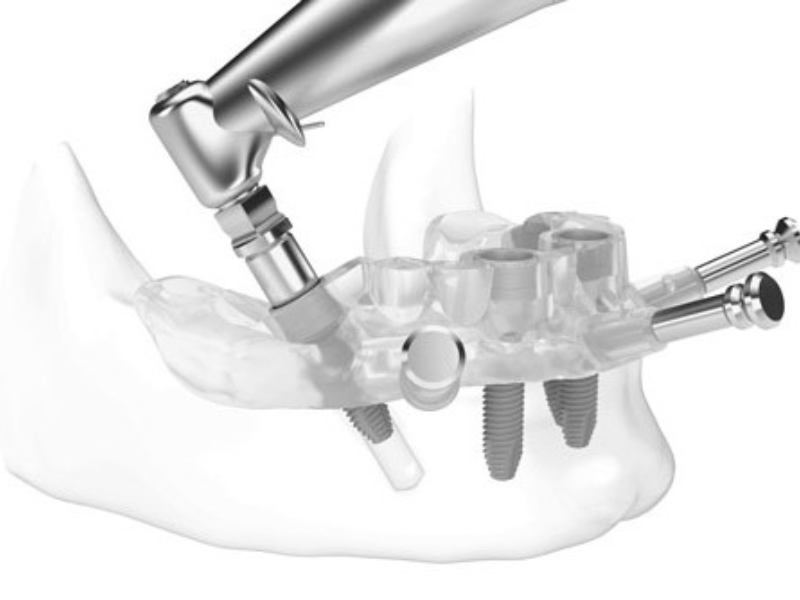

Cirurgia guiada é uma tecnologia avançada que permite aos cirurgiões realizarem procedimentos cirúrgicos com maior precisão e segurança. Esta tecnologia envolve a utilização de um sistema de navegação guiado por computador que fornece informações importantes ao cirurgião durante o procedimento cirúrgico. Os médicos utilizam o sistema de navegação para criar e acompanhar um plano cirúrgico preciso, o que permite que eles executem o procedimento com maior precisão e segurança.

O sistema de navegação de Cirurgia Guiada é composto por vários dispositivos que permitem que o cirurgião monitore a localização de instrumentos cirúrgicos no corpo do paciente durante o procedimento cirúrgico. Estes dispositivos incluem sensores de movimento, imagens de raios-X, ultrassom e até dispositivos laser. A Cirurgia Guiada permite que o cirurgião use um monitor para visualizar e acompanhar a localização de instrumentos cirúrgicos dentro do corpo do paciente.